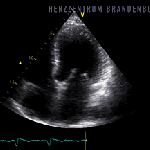

„Auf dem Weg in die Katastrophe“ – Herzerkrankungen als Folge von COVID-19-Impfung nehmen in Israel dramatisch zu

Wir sehen in vielen Ländern dasselbe Muster. Es wird geimpft auf Teufel komm‘ raus. Jede Vernunft und jede wissenschaftliche Erkenntnis bleiben dabei auf der Strecke. Wer es anmerkt, der wird ignoriert, zensiert, verfolgt oder von gedungenen Faktenmördern zu diskreditieren versucht. Dabei häufen […]